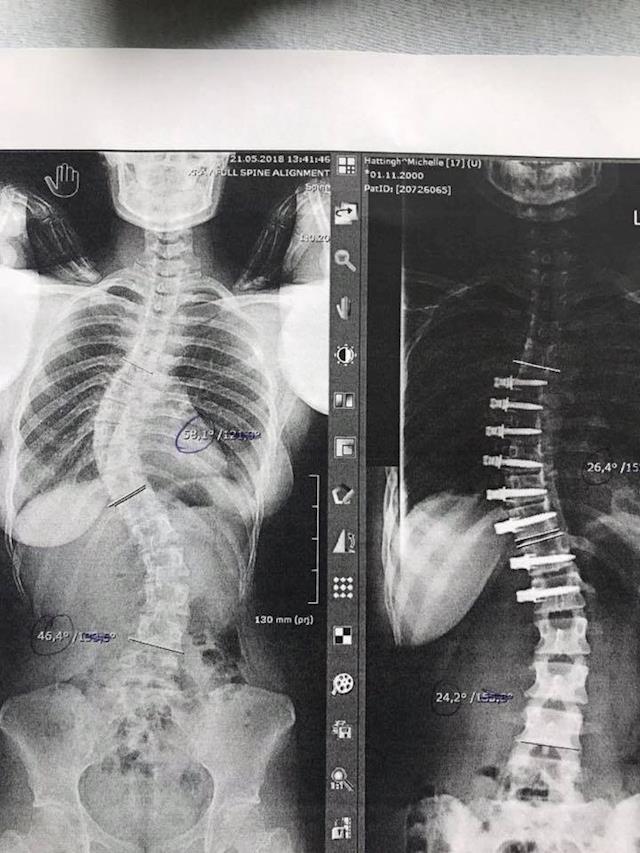

We are very pleased with the outcome and progress so far. The curve correction is over 50%. I have attached the latest X-Ray. We were super stoked with the results. She has 8 screws and the nylon tether which should keep the spine in place and prevent further progression. In fact it should over time straighten a bit more. It will also leave her with flexibility and the ability to do almost anything that she could do before surgery.

This is opposed to traditional fusion that would have left her with 16 screws and two steel rods with all the bones that would over time fuse together - leaving her less flexible, but also in risk of second surgery.